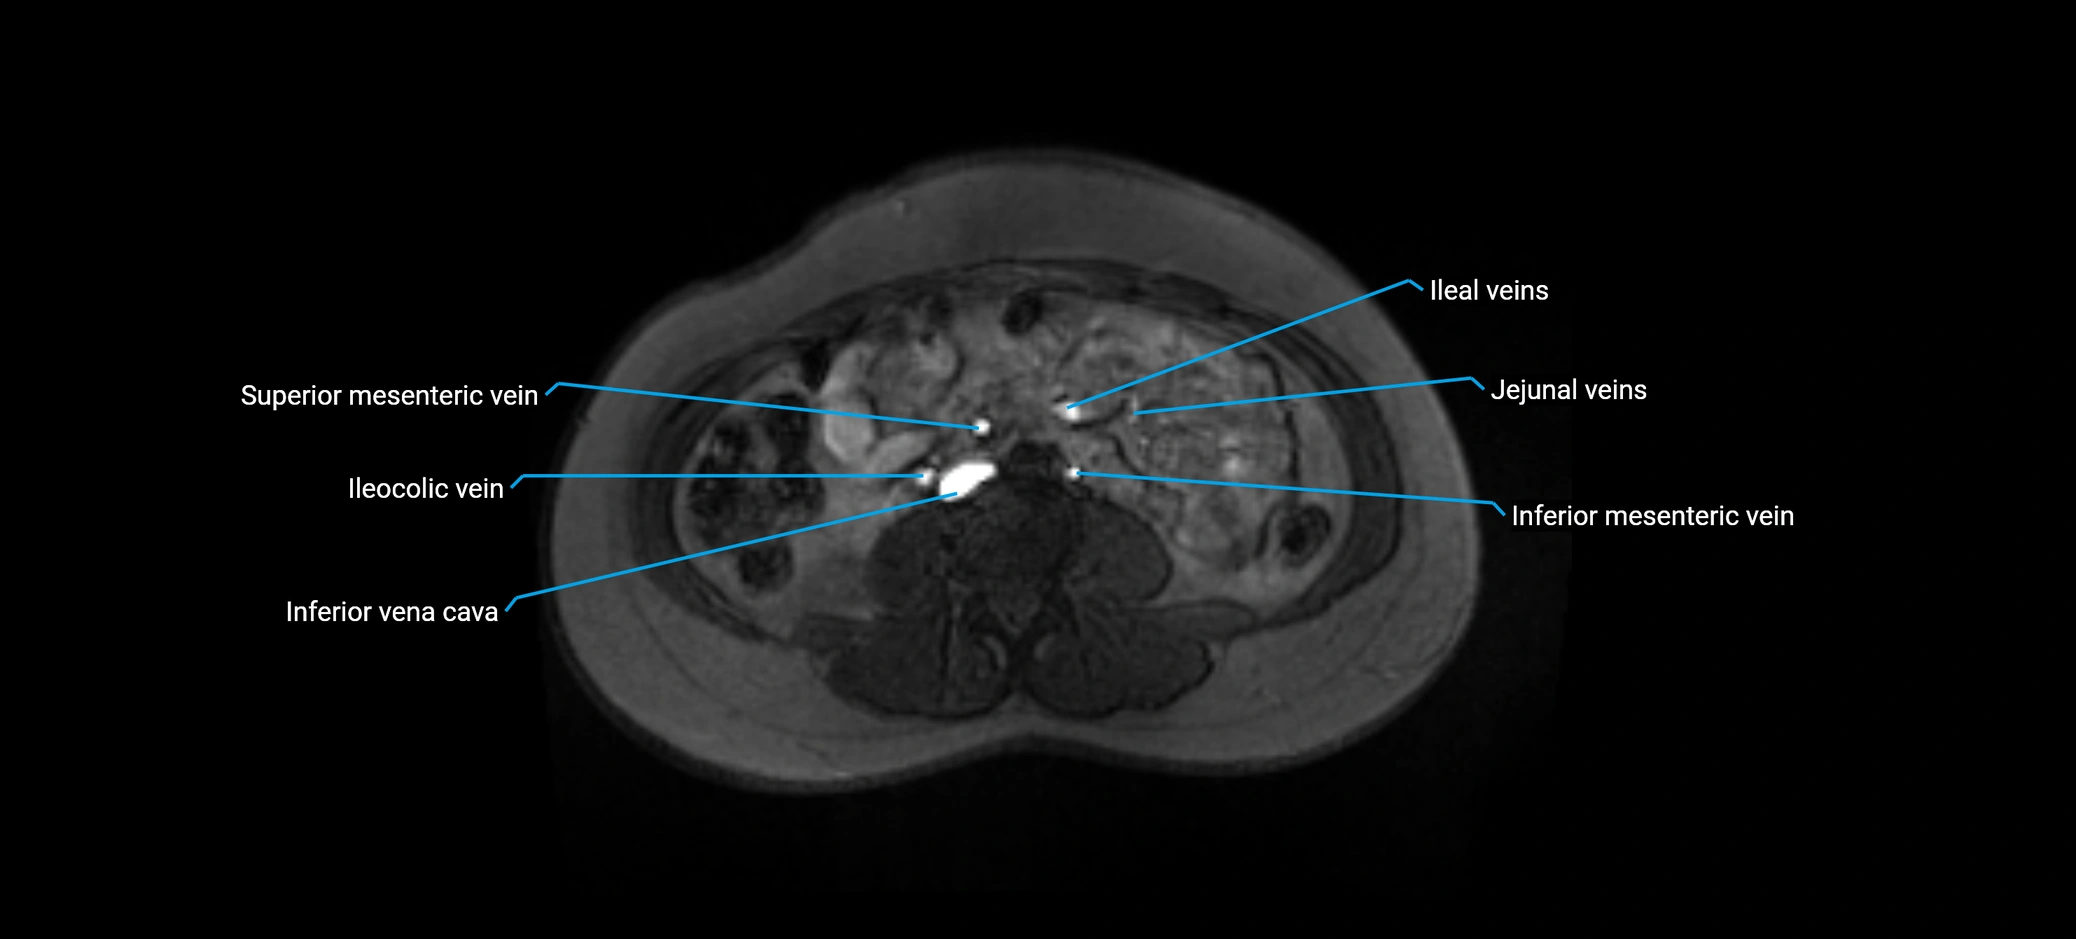

MRI image

image